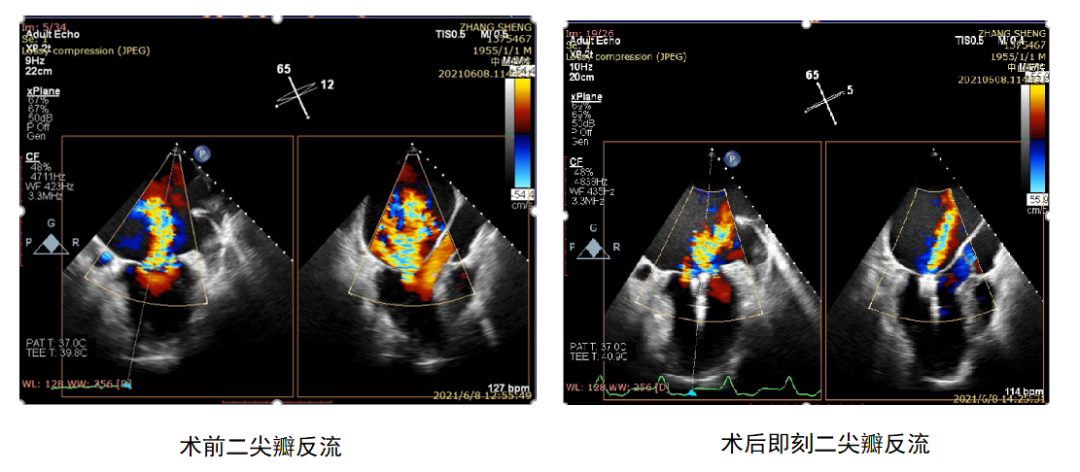

二尖瓣反流介入治疗的超声心动图评价中国专家共识

世界首例王春生魏来教授团队成功实施功能性二尖瓣反流经心尖缘对缘